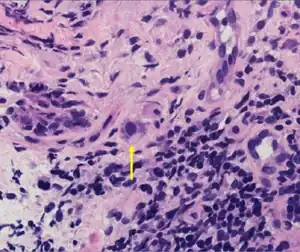

| Typical "owl eye" intranuclear inclusion indicating CMV infection of a lung pneumocyte[1] | |